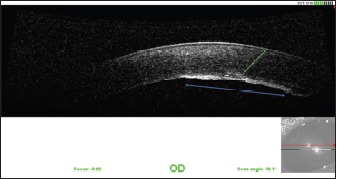

Fig. 9. OCT of the cornea 1 year after the surgery. Note the fibrous metaplasia of the endothelium (blue arrow) and probable duplication of the Descemet membrane (green arrow).

The various follow-up visits revealed improvement in comfort, with the disappearance of the blepharospasm. The corneal edema was greatly improved. The visual tests were positive and the intra ocular pressure (IOP) was stable. Six months after the surgery, the observable sequelae were the persistence of discrete corneal edema in the area of the point of penetration of the claw as well as dyscoria (Fig. 6). The tear area of the endothelium and Descemet membrane was still visible at high magnification (Fig. 7). One year after the surgery, the vision tests were positive. The cornea had fibrosis at the point of impact and opposite the endothelium and Descemet membrane tear, which was still visible (Fig. 8). The pupil was slightly deformed and the capsule of the lens was partially fibrosed. Optical coherence tomography (OCT) of the cornea revealed fibrous metaplasia of the endothelium and probable duplication of the Descemet membrane. The intraocular pressure was measured to be 13 mmHg by rebound tonometry (Fig. 9).

The tear of the endothelium and Descemet membrane caused significant corneal edema by imbibition of the stroma by the AH, visible at the follow-up visit at 1 week. The various follow-up visits showed favorable progression of the edema, with an almost total disappearance at 9 months after the surgery. The endothelial phase of corneal healing normally begins 24 hours after trauma (Whitley and Hamor, 2021). In adult dogs, endothelial cells are incapable of mitosis (Befanis et al., 1981). The endothelium heals mainly by rearrangement of the cytoskeleton of the cells that compose it. The latter then occupy a larger surface area and migrate by sliding to fill the deficit related to the trauma. The density of endothelial cells decreases after trauma. Endothelial cells undergo fibrous metaplasia and produce a new Descemet membrane after a few weeks (Whitley and Hamor, 2021). Duplication of the Descemet membrane may occur after perforating trauma to the cornea (Kafarnik et al., 2009). In our case, endothelial compensation allowed the maintenance of corneal deturgescence during the follow-up period, thus ensuring the maintenance of satisfactory vision for the patient. The tear of the endothelium and Descemet membrane nevertheless remained visible by slit lamp at the check-up visit at 1 year.